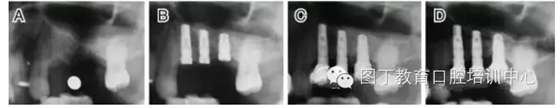

臨床上,可使用曲面體層放射線法及CT掃描方法對(duì)上額竇及可用骨量進(jìn)行評(píng)估。其中曲面體層放射線法可提供多數(shù)病例的硬腭致密影像,為治療計(jì)劃提供有價(jià)值的參考(圖1);而使用CT掃描可提供骨密度信息。如骨高度、密度、牙槽嵴的方向位置,皮質(zhì)骨和松質(zhì)骨的特點(diǎn),上頜竇黏膜厚度,病理狀態(tài)等。顯然,在上頜竇底提升術(shù)中,CT掃描影像的信息對(duì)于手術(shù)設(shè)計(jì)和減少治療風(fēng)險(xiǎn)非常重要。

圖1 采用曲面體層放射線法評(píng)估